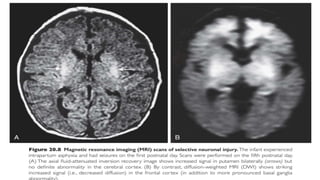

MRI

• Best modality for determining the severity and extent of irreversible

hypoxic ischemic brain injury

• Conventional sequences best for detection of brain injury in the 1st 7

days, and a scan as late as 14 days or beyond may be needed to show

the full extent of injury

• Diffusion-weighted imaging (DWI) can show abnormalities within

hours of an early HI insult that may be useful in the diagnosis of

neonatal HIE and an early indicator of possible brain injury

• DWI can underestimate and overestimate the severity of brain injury depending on

the timing of the study

• Early DWI scans: restricted diffusion in the affected brain regions

• 7-10 days of age: pseudonormalization of diffusion, so DWI can be normal despite

the presence of HI injury

• After 7-10 days, diffusion increased in the regions of injury

• Certain distributional patterns of brain injury which may be typical of

HI injury are:

- Injury to deep gray nuclei especially the posterior putamen and

anterolateral thalami

- Parasaggital injury of cerebral cortex and subcortical white matter in

the arterial watershed distribution

• Early brain MRI (1-5 days) is useful for:

- Detection of early restricted diffusion that indicates early HI injury

- To assess if injury is already well established (antenatal vs perinatal)

- To establish any potential etiology of encephalopathy besides HI

- To begin to assess the presence/severity of Hi injury

• Late MRI scans useful to detect the severity and location of the injured

areas, best determined by conventional T1 and T2 weighted imaging

sequences at 10-14 days or beyond

DWI sequences will show increased diffusion in affected areas